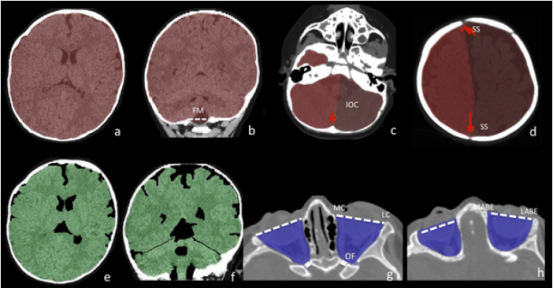

图 5:颅内腔和眼眶的体积分析。颅内体积(ICV):用红色阴影区域表示(图 a 和 b)。ICV 包括从枕骨大孔到颅顶的整个颅内腔。图中勾勒出颅骨内板与脑表面的界面。

半颅内体积(Half ICV):用亮红色和暗红色共享区域表示(图 c 和 d)。矢状缝(图 d 中的箭头)和枕内嵴(图 c 中的箭头)是中线标志,用于将一侧的半 ICV 与对侧分开。

全脑体积(WBV):用绿色共享区域表示(图 e 和 f)。WBV 包括大脑半球、中脑、小脑和脑干(至枕骨大孔水平),不包括脑室和脑周围蛛网膜下腔。

眼眶体积(OV):用蓝色共享区域表示(图 g 和 h)。眼眶的后界由视神经孔(OF)内侧壁和外侧壁的连线定义(图 g 中的虚线)。眼眶腔的前界在适当切片中由内眦(MC)和外眦(LC)之间的连线定义,在其余切片中由内侧和外侧眼眶壁最前骨缘之间的连线定义(图 g 和 h 中的虚线)。